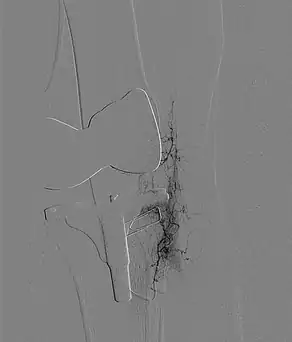

Innovativ ging es weiter mit Dr. Guido Zintl (Oberarzt der Radiologie am GK-Bonn). Er stellte die noch relativ junge operative TAPE-Therapie als neue Hoffnung für Arthrose-Patient:innen vor.

Bei Kniearthrose führen chronische Fehlbelastungen und Entzündungsreize häufig dazu, dass sich im Gelenk zusätzliche feine Blutgefäße und krankhafte Nervenfasern entwickeln, die Schmerzreize ans Gehirn übermitteln. Betroffene sprechen oft schlecht oder gar nicht auf Medikamente an, sodass diese nur begrenzt Linderung bringen.

Das schonende TAPE-Verfahren (Abkürzung für transarterielle periartikuläre Embolisation) bietet hier Hilfe: Durch den vorübergehenden Verschluss der überzähligen Gefäße werden Nervenschmerzen stark vermindert oder sogar gestoppt. Die gesetzlichen Krankenkassen übernehmen bei passender Indikation die Kosten für diese schonende Operation mittels Mikrokatheter.